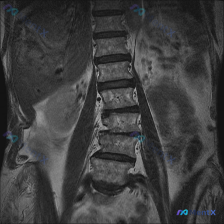

整理到一张腰椎MRI的冠状位T1WI图像,先不说结论,大家第一眼会怎么看? 目前能看到的影像表现: - 腰椎明显向右侧凸,有椎体旋转和倾斜 - 两侧椎间隙高度不均匀,部分变窄 - 多个椎间盘信号降低 - 椎体骨髓信号基本是弥漫中等偏高,没看到明确的局灶骨质破坏或大肿块 - 两侧腰大肌形态不对称 这份...